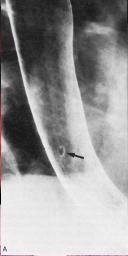

Image papilome oesophagien ( en

fleche ) . TOGD ++ double de contrast bryte |